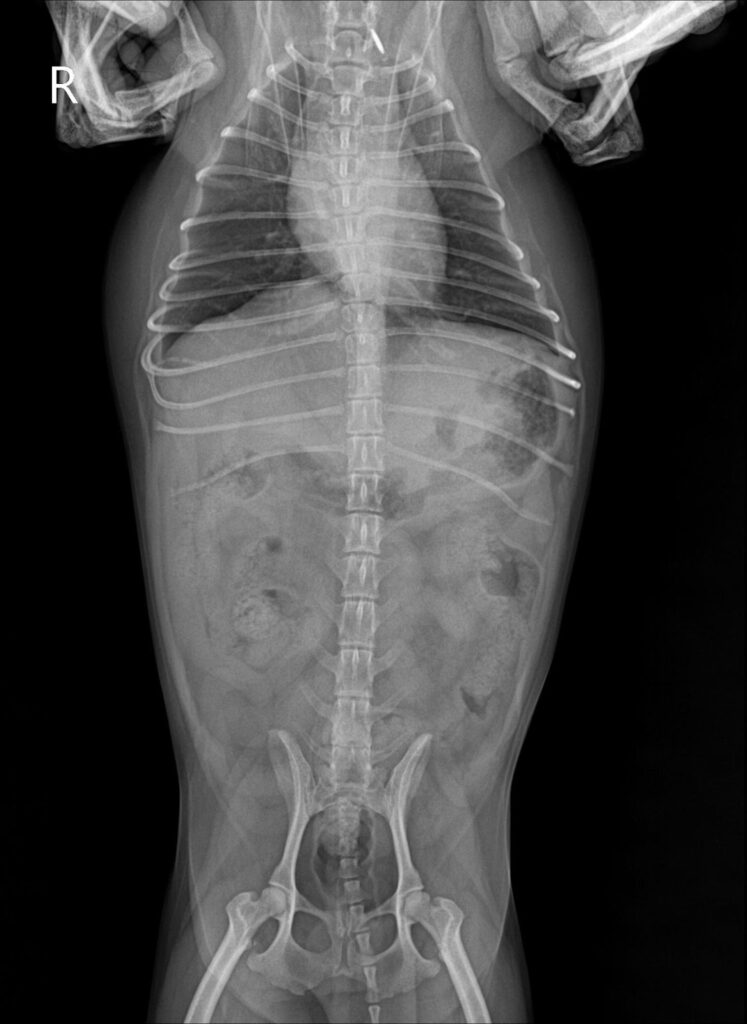

슬개골 촉진 검사에서 양측 슬개골 모두 내측 탈구가 확인되었고, 우측은 2–3기, 좌측은 4기로 진단되었습니다. 엑스레이 검사에서도 무릎뼈가 대퇴골 고랑을 벗어나 내측에 위치한 모습이 명확히 관찰되었습니다.

수술 전 X-ray 사진 / 출처: 미래동물의료센터